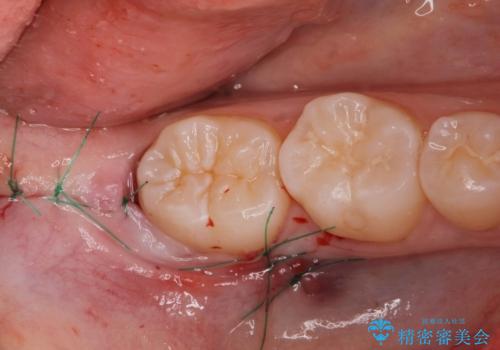

歯の高さを出すための親知らず抜歯と歯肉切除

担当医 岡田康成